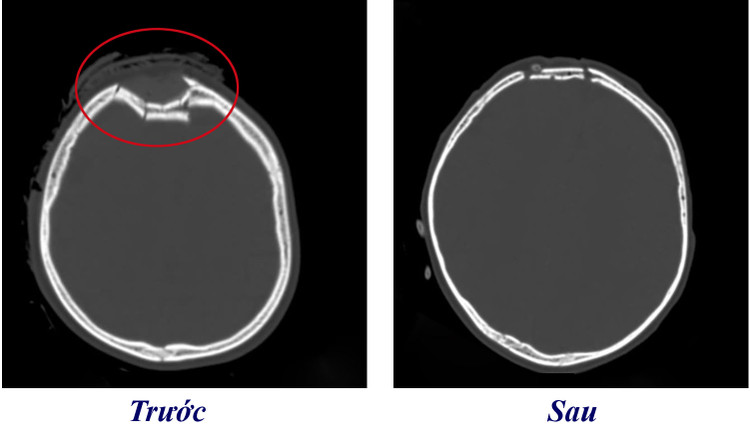

| Phim chụp sọ não bé trước và sau khi phẫu thuật. Ảnh BVCC |

Tại bệnh viện, qua thăm khám, các bác sĩ phát hiện trên phim chụp CT.Scanner sọ não bệnh nhi bị vỡ lún xương sọ trán phải, đụng dập tụ máu nhu mô não trán phải.

Bệnh nhi được phẫu thuật nâng lún xương sọ, cầm máu và xử trí vết thương. Hiện tại sau phẫu thuật sức khỏe bệnh đã ổn định đang tiếp tục được theo dõi, điều trị tại bệnh viện...